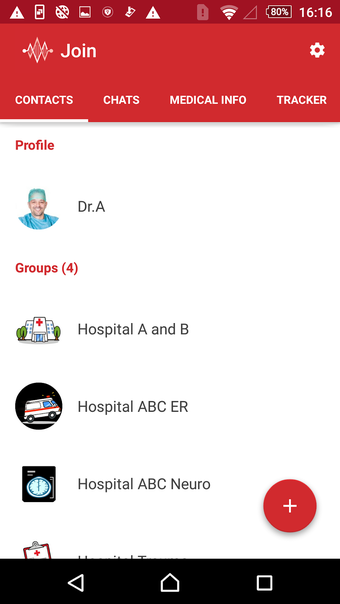

Join adalah aplikasi berbasis awan yang digunakan oleh para profesional dan penyedia layanan kesehatan untuk berkomunikasi secara aman dan berbagi informasi pasien. Aplikasi ini telah dikembangkan oleh perusahaan kami, dan dapat digunakan bersamaan dengan sistem catatan medis elektronik yang kompatibel (EMR atau EMR*).

Untuk memberikan perawatan terbaik bagi pasien, para profesional kesehatan perlu memiliki akses cepat dan mudah ke riwayat medis pasien, termasuk data laboratorium, resep obat, dan laporan radiologi. Dengan Join, mereka dapat dengan mudah mengirimkan gambar rekam medis pasien kepada rekan mereka, sehingga mereka dapat dengan cepat dan efisien membuat diagnosis dan rencana perawatan.

Join juga memungkinkan mereka untuk berkomunikasi dengan rekan mereka tentang kondisi pasien, yang sangat penting untuk memberikan perawatan terbaik.